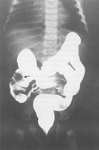

Estudo de trato gastrointestinal superior com contraste revelando má rotação com volvo. O duodeno não é capaz de desenvolver a alça anatômica normal em forma de C. Há falha na passagem do contraste, resultando em bico de pássaro característico consistente com volvo do intestino médio agudo

Do acervo de Dr. KuoJen Tsao; usado com permissão